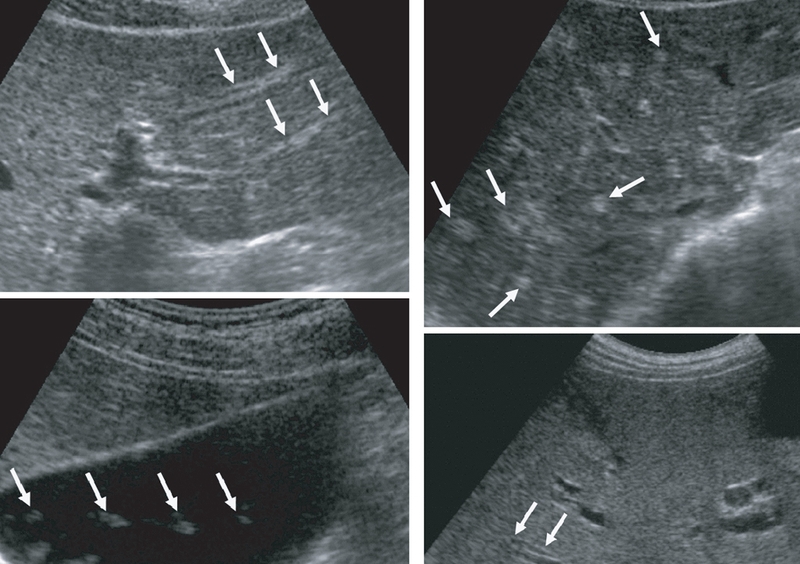

Các loại xét nghiệm thường được dùng để chẩn đoán bệnh sán lá gan lớn gồm: